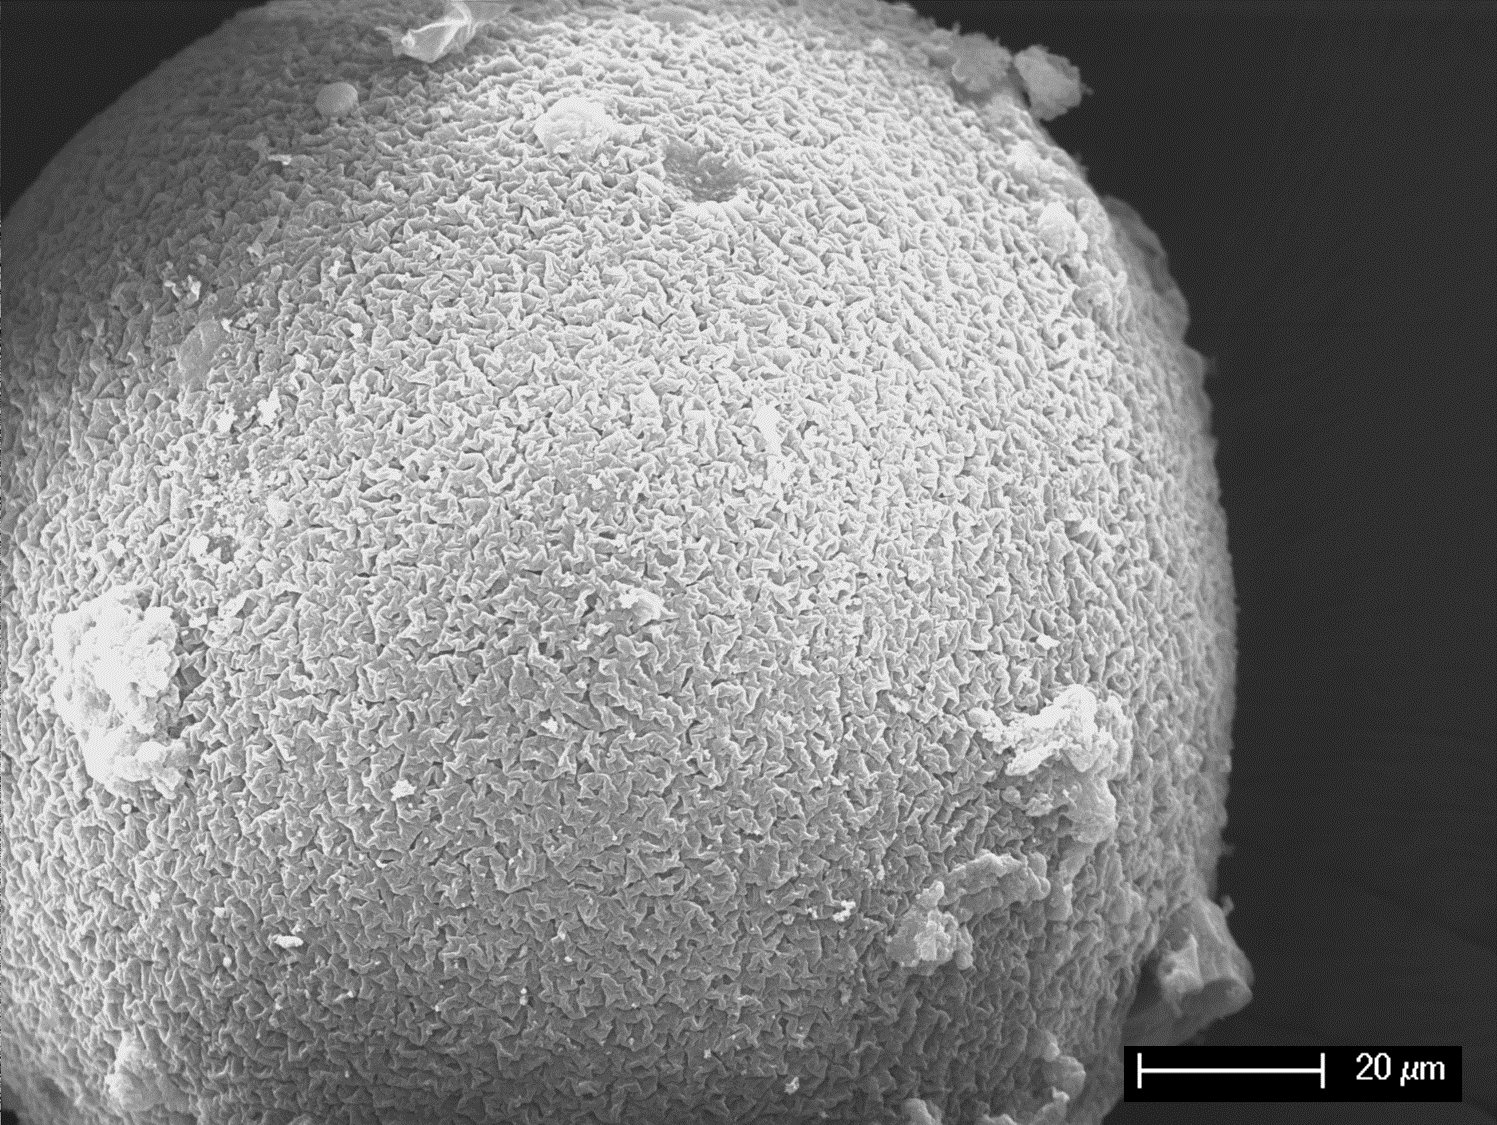

Extracorporeal blood purification techniques represent a therapeutic approach to clinically support patients suffering from specific pathological conditions. These systems aim at the removal or at the modulation of molecules responsible for the disease state. The treatment may be performed by circulating whole blood (hemapheresis) or plasma (plasmapheresis) in membrane-adsorption systems. The depletion of the target molecules is based on physical adsorption, chemisorption, or ion exchange. Cytokines are potential targets for adsorption in conditions associated with systematic inflammation, such as sepsis and septic shock. The aim of this project is to create a universal blood-compatible carrier to be used as basic matrix in hemosorption. Particularly, this project focuses on the development, characterization and optimisation of (1) novel porous poly(styrene-co-divinylbenzene-co-vinylbenzyl chloride) (PS/DVB/VBC) hypercrosslinked beads and (2) tris(hydroxymethyl)aminomethane (Tris) derivatized (PS/DVB/VBC-Tris) beads with hydrophilic surface prepared by suspension polymerisation for application in extracorporeal cytokine removal. The innovative aspect of this project is the particular attention paid to the mechanism by which adsorbent properties may induce thrombocyte activation and adhesion as well as release of extracellular vesicles from activated blood cells. Therefore, we will not only focus on the cytokine removal, but also on indicators of hemocompatibility, such as endothelial activation, hematological parameters, thrombocyte activation/adhesion and release of extracellular vesicles. In conclusion, this study will give an overview about cytokine adsorption capacity and hemocompatibility of the newly developed PS/DVB/VBC based adsorbents. The results acquired in this project will allow us to correlate the physiochemical parameters to cytokine adsorption capacity and blood compatibility of the PS/DVB/VBC based polymers for extracorporeal cytokine adsorption. The project will be divided into 4 work packages: 1) PS/DVB/VBC beads preparation and characterization (lead partner UM); 2) PS/DVB/VBC-Tris beads preparation and characterization (lead partner UM); 3) Characterisation of Adsorbents for Cytokine Removal from Plasma and Whole Blood (DUK); 4) Evaluation of Hemocompatibility of PS/DVB/VBC-Tris beads with hydrophilic surface (DUK).